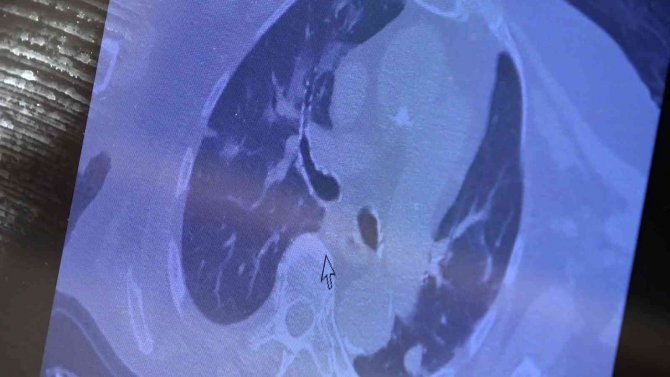

81 yaşında akciğer tutulum olan hastanın tomografisi

Karşılaştıkları bu yeni hasta profilini örnek vererek açıklayan Özkaya, "81 yaşındaki bir hasta. Ailesinde kovid pozitif biri varken panik yaparak aşıya gidiyor. Sonrasında hızla akciğer tutulumu olan bir hasta ile karşılaşıyorsunuz. Bu şekilde ailenizde pozitif biri varsa ve kendinizde halsizlik kırgınlık hissediyorsanız panik yapmadan önce doktora gitmenizi sonra aşı olmanızı istiyoruz. Şu an "aşı oldum hastalandım" diyenlerin büyük bir kısmı subklinik olarak virüsle enfekte iken aşı olan grubu oluşturuyor" şeklinde konuştu.